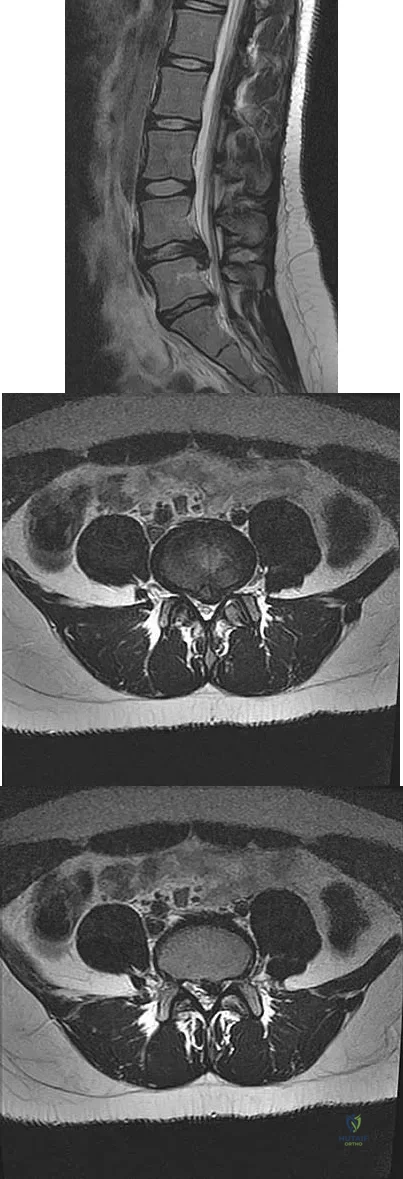

A 50-year-old man with no history of trauma reports new-onset back pain after doing some yard work the previous day. He reports pain radiating down his leg posteriorly and into the first dorsal web space of his foot. MRI scans are shown in Figures 3a through 3c. What nerve root is affected?